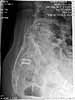

Patient is a 61 y/o referred with chronic R SIJ pain. Had "fusion" in 1997. R posterior iliac crest harvested. Still has pain on daily basis. On days it is as high as a 9, others it is as low as a 4, but always is present. She also describes occasional pain down the anterior part of her thighs. She has certain activities that aggravate it and certain activities that do not. When discussing things with her, the pain is really mostly directly in the area of the cage placement.She has tried multiple other modalities to achieve some relief including acupuncture, PT, water walking, TENS, magnetic therapy, lotions, ice, and injections. None of these have given her adequate relief. Prior to attempted SI joint fusion, she had an injection in the joint, which seemed to eliminate her symptoms, and after the attempted fusion she had another injection, which seemed to help as well. That is why she thinks she has persistent pain from this joint. Any thoughts?

Interesting way of fusing the SI joint! I would have probably tried SI screw or anterior fusion instead. Even though the "fusion" looks good from the cage insertion, mechanically, I do not know how much stability is provided. Have you obtained a bone scan recently to see if corresponding uptake noted? Have you tried a lidoderm patch? Any response from a medrol dose pack? How did you have this "interesting" and "educational" patient end up on your doorstep? A complex problem in which even if joint is truly stable and fused, she may always have "problems" that surgery and PT may never remove.

I have seen a couple of patients with the BAK used for SI fusions, they were not helped at all.

there do not appear to be any stress fractures of the iliac wing related to the bone graft on these images.

The CT shows a solid bone mass but the true articular part of the joint remains. This may be a red herring.